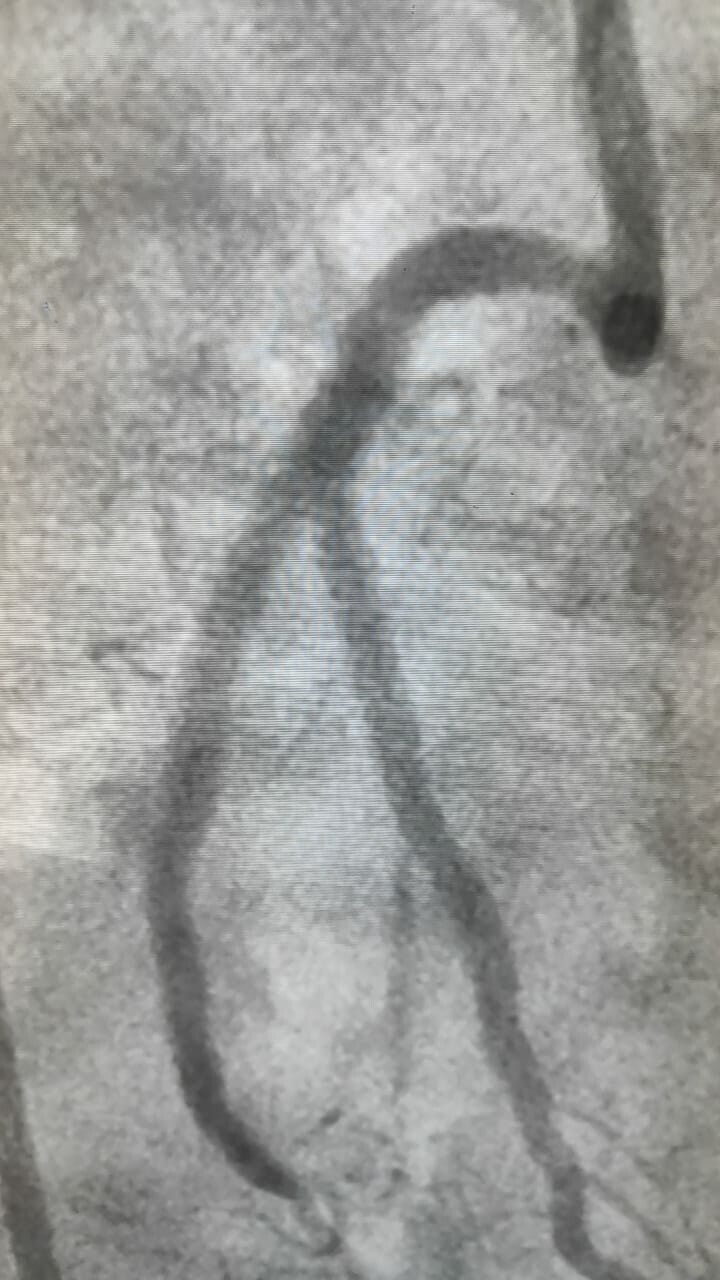

Successful Complex Bifurcation Angioplasty by Dr. Hasmukh Gujar

Efficiently performed complex bifurcation angioplasty by Dr. Hasmukh Gujar has resulted in the patient's excellent recovery and well-being. Expert car...